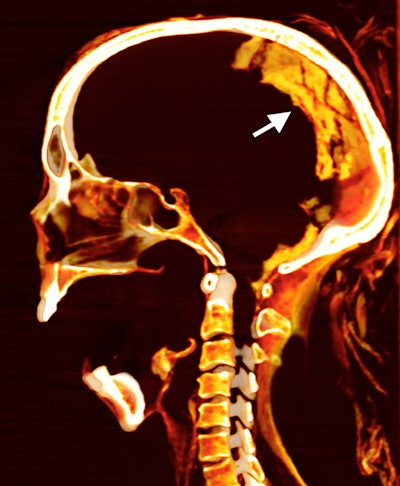

CT shows the brain inside the skull of the "Screaming Woman" mummy.

Saleem used CT imaging to "virtually dissect" the mummified woman. The authors also used scanning electron microscopy (SEM), Fourier transform infrared spectroscopy (FTIR), and x-ray diffraction analysis (XRD) to classify materials related to the body.